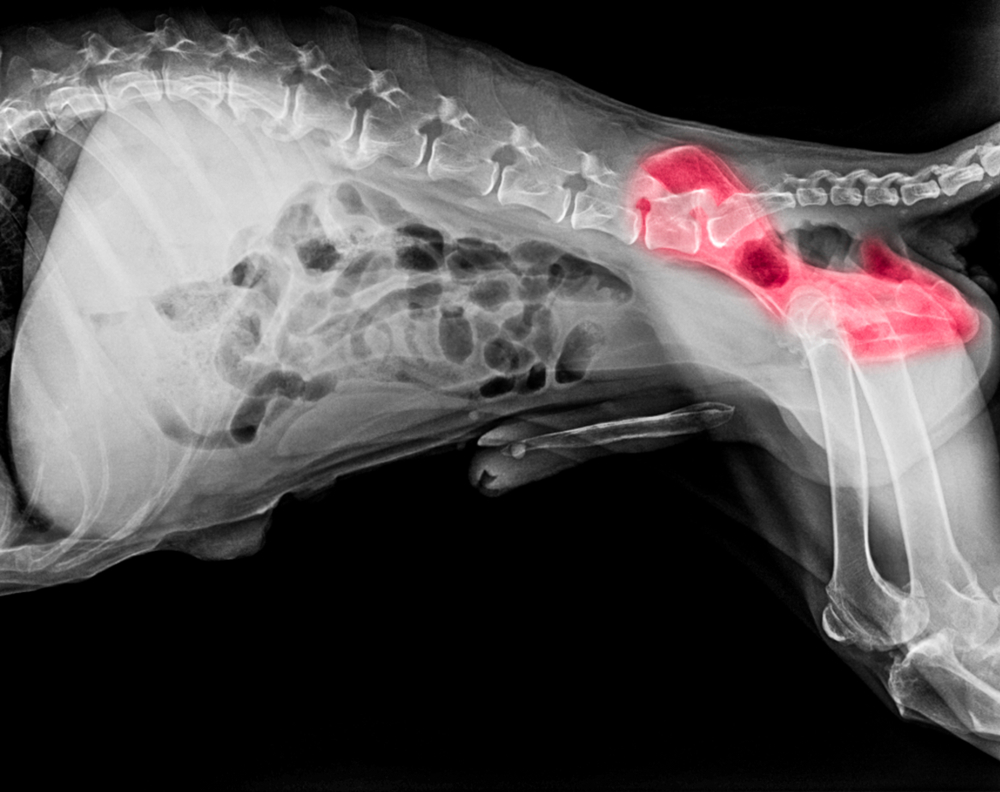

• X-rays — Our team takes X-rays to visualize the hip joint and assess the dysplasia’s severity.